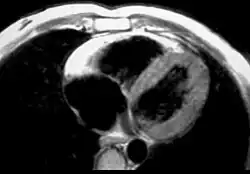

MRI in a patient affected by ARVC/D (long axis view of the right ventricle): note the transmural diffuse bright signal in the RV free wall on spin echo T1 (a) due to massive myocardial atrophy with fatty replacement (b).